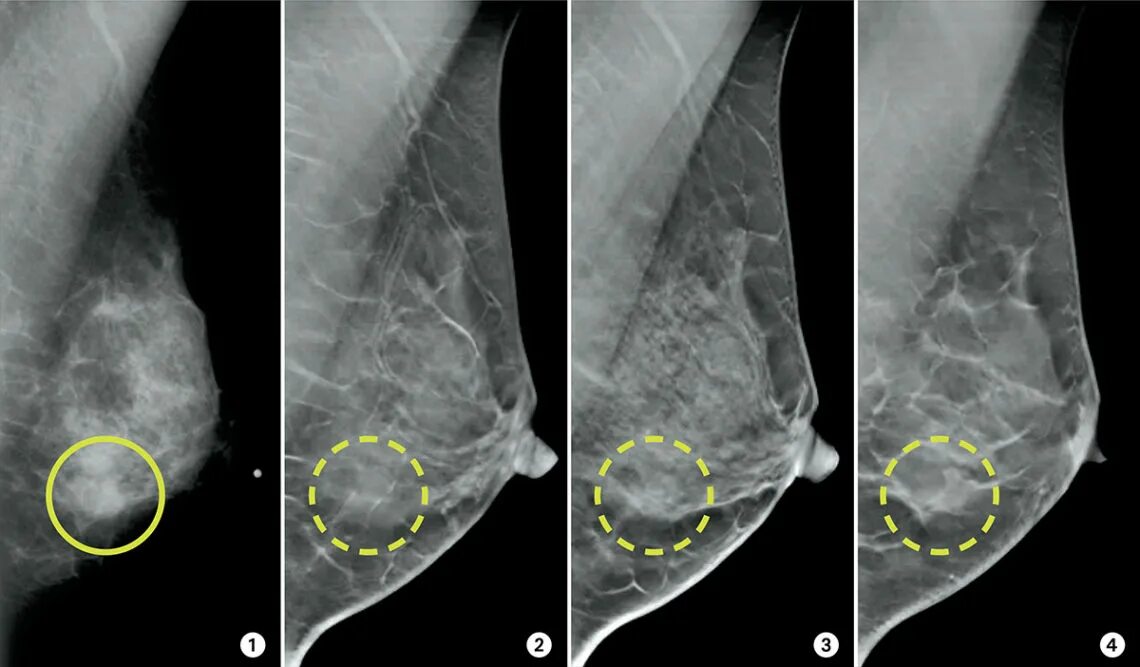

Метастазы молочной железы симптомы